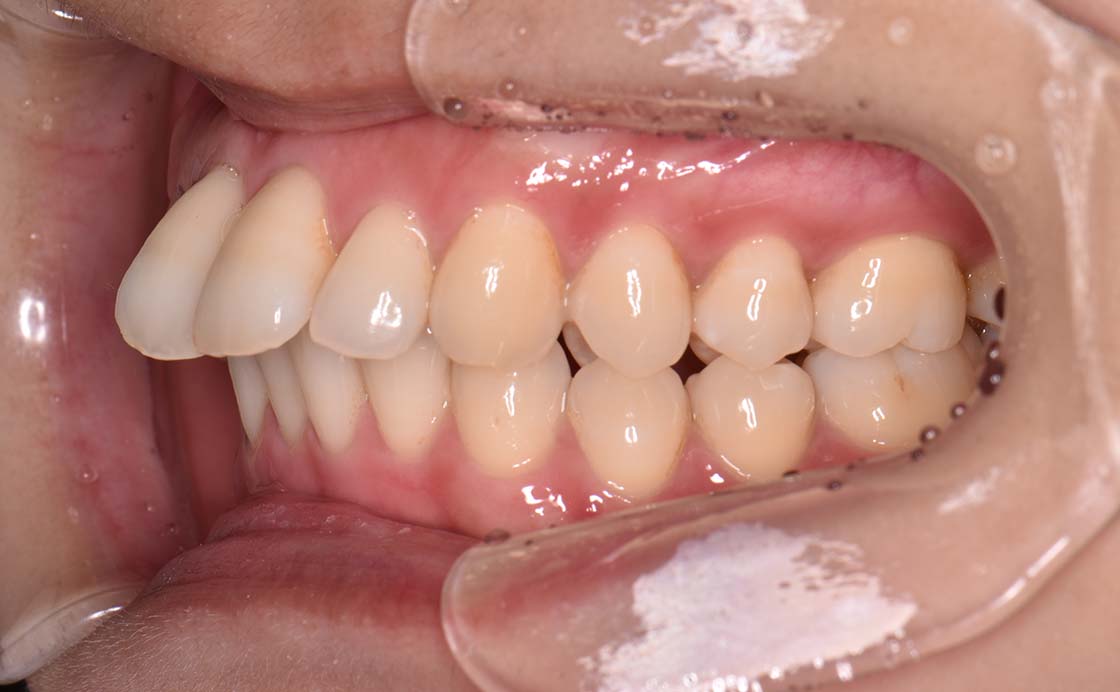

上顎前突とは上の前歯が前方に突出している状態をいいます。顎や歯の前後的位置のズレのため生じ、成長期には顎や歯の成長をコントロールすることで治ります。また永久歯列の場合には抜歯が必要になることがあります。